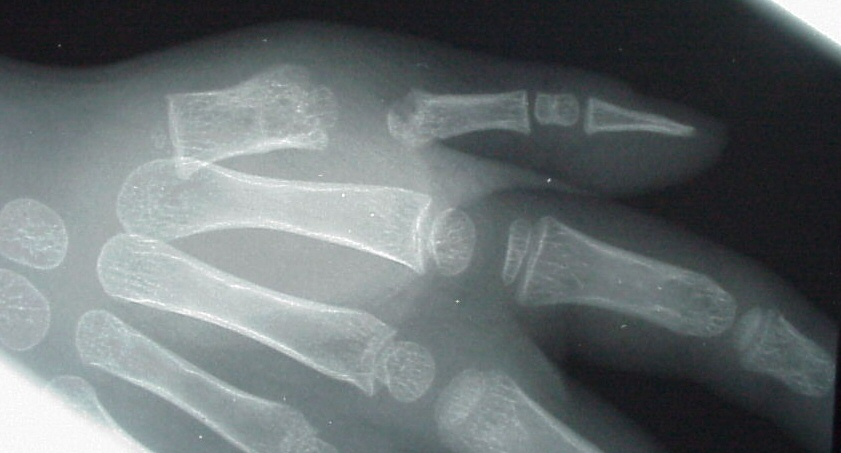

| Case 1. Wassell IV duplication of the proximal and distal phalanges, with characteristic deviation of the thumbs away from each other at the MCP and toward each other at the IP joints. This was corrected by metacarpal head narrowing, opposing closing wedge osteotomies of the metacarpal and proximal phalanx and collateral ligament reconstruction using parts from the deleted digit. |